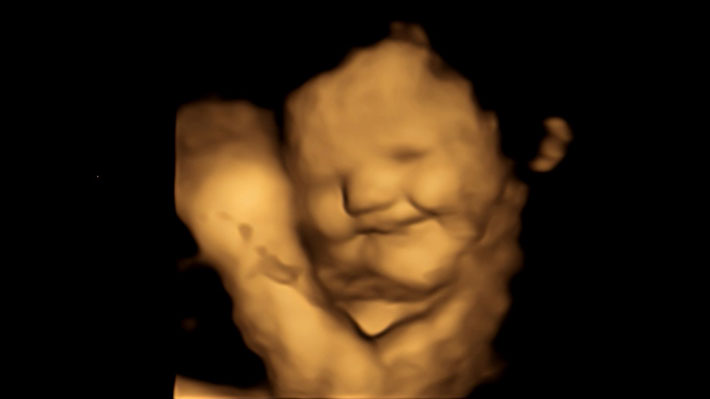

Los investigadores analizaron sus reacciones faciales a través de ecografías 4D realizadas poco después de sus madres ingirieran ciertos alimentos.

Los fetos que fueron expuestos al sabor de la zanahoria mostraron más respuestas de "cara de risa".

La expresión de la cara de un grupo de bebes aún no nacidos, captada a través de ecografías en 4D, constituye la primera evidencia directa de que el feto reacciona a los sabores de los alimentos que consume la madre.

Los fetos expuestos a la zanahoria mostraron más respuestas de "cara de risa", mientras que los expuestos a la col rizada mostraron más respuestas de "cara de llanto", explicó la universidad.